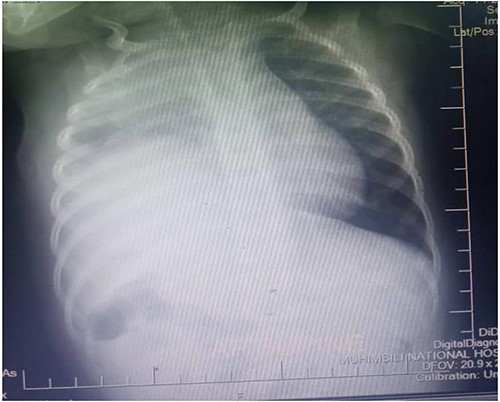

Thus, the tube thoracostomy with under water seal drainage was performed and supportive oxygen therapy was initiated accordingly. In the second day postadmission, the respiratory symptoms resolved and she was weaned off oxygen and other supportive therapies were reduced. Later a whole-body CT scan was performed and admitted in Paediatric Surgery ward in Muhimbili National Hospital. The CT scan revealed a hypodense fluid collection on the right hemithorax, 33HU associated with ipsilateral pulmonary atelectatic changes, discontinuity of the right hemidiaphragm with intrathoracic herniation of the liver that appeared to be normal in size. Nevertheless, the child was in good condition, without respiratory distress or bowel obstruction.

Figures 2 and 3 axial views of thoraco-abdominal CT image taken before laparotomy revealing a ruptured diaphragm of a 1-year-old post trauma patient with reduced right lung volume of expansion.